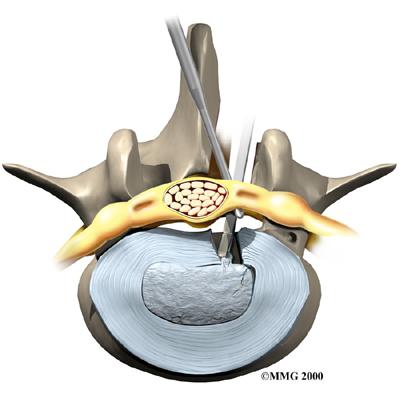

Microdiscectomy

Microdiscectomy is becoming the standard surgery for lumbar disc herniation. The procedure is used when a herniated disc is putting pressure on a nerve root. It involves carefully taking out part of the problem disc (discectomy). By performing the operation with a surgical microscope, the surgeon only needs to make a very small incision in the low back. Categorized as minimally invasive surgery, this surgery is thought to be less taxing on patients. Advocates also believe that this type of surgery is easier to perform, that it prevents scarring around the nerves and joints, and that it helps patients recover more quickly.

Related Document: FYZICAL Delran's Guide to Lumbar Discectomy